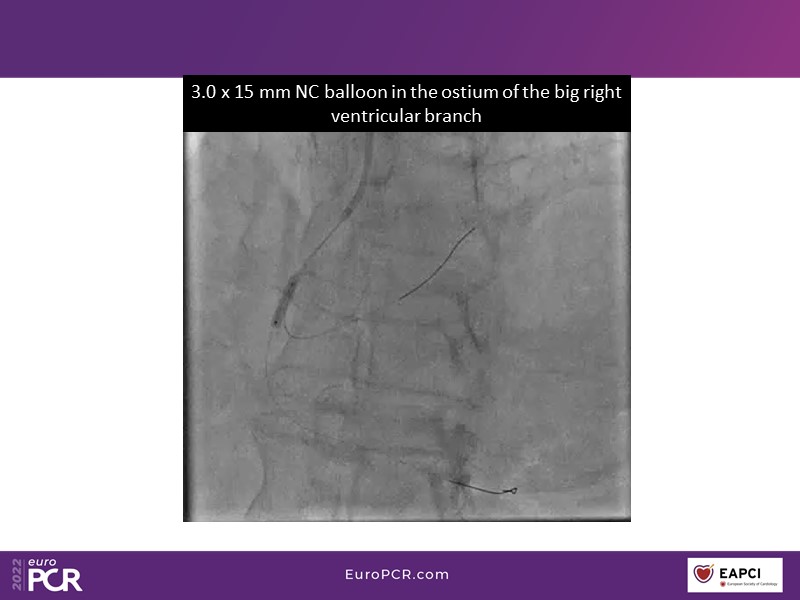

Alexandre Abizaid, Marco Valgimigli, Fazila Malik, Luca Testa, Patrick W. Serruys, Damiano Regazzoli, Kumar Prathap, and Sandeep Basavarajaiah take turns in this session to discuss two innovative technologies: a stent platform with nanotechnology and a novel drug-coated balloon (DCB). These novel technologies both have unique features that could change daily practice and improve outcomes.

- To find out more about the application and mechanism of a sirolimus coated balloon for coronary artery disease treatment with case presentations in complex settings

- To understand how useful is a DES and DCB stent platform in complex coronary artery disease settings with case demonstrations and follow-up in diabetes mellitus